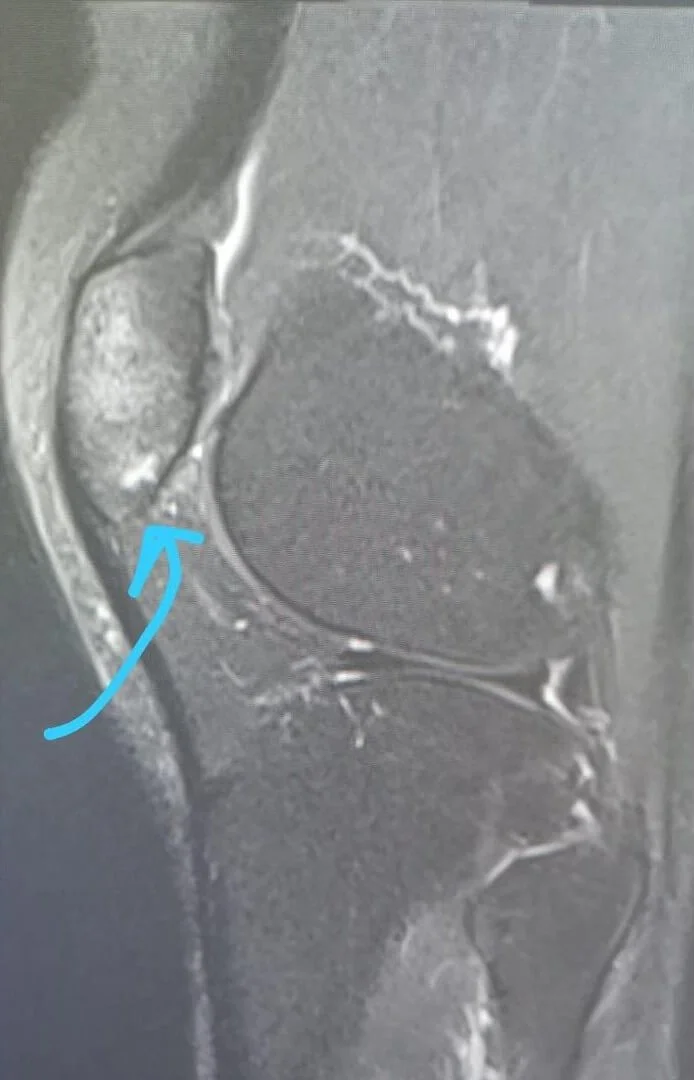

林欣彤(Mag)上月放狗時,愛犬「飛飛」突然失控奪命狂奔,突如其來的衝力令她跌倒受傷。傷後幾天,Mag在IG發文報平安,傷勢康復進度理想,之前又現身《聲夢傳奇》,擔任文凱婷的導師一起演出,活動自如,以為已接近痊癒,但今日(22/06),她卻上載一張X光照片,透露最近傷勢,「原來我嘅膝頭哥底真係骨裂咗‥‥‥」Mag才恍然大悟,為何傷後一整個月仍未痊癒,又笑言:「可能因為我嘅忍耐能力比較強一點點‥‥‥所以大家都話應該唔係骨裂嘅如果唔係會痛到點點點‥‥‥所以一直都冇照任何嘢,抖左一星期我就繼續照行照郁照做家務照工作,所以以為骨應該冇事~」

由於她希望恢復運動,才決定求醫照X光,並打算檢查完後去跑步,豈知事與願違,醫生建議她暫時不要穿高踭鞋,盡量休息,不要做運動,令她甚難受,高呼:「天啊!!!幾時先好返‥‥‥我想跑步我想做深蹲我想操腿肌‥‥‥」不過Mag性格堅強,表示自己的輕微骨裂只是小兒科,叫大家不用誓心,並呼籲為她集氣,盡快康復,「因為我想做運動,有健全嘅身體係好值得感恩。」

圖片來源:林欣彤@Instagram